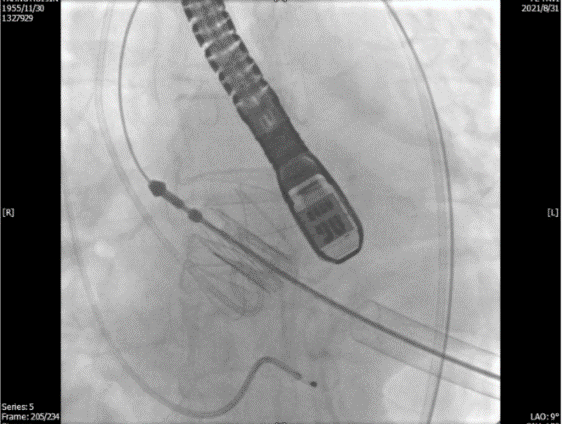

透视下定位后第五肋间小切口进胸,打开心包,选择心尖裸区缝制六边形荷包。心尖穿刺后将泥鳅导丝过主动脉瓣经升主动脉、主动脉弓到达降主动脉膈肌水平,通过TEE确认细导丝没有与二尖瓣腱索缠绕(图2)。

图2. TEE和放射线显示输送器进入升主动脉根部、瓣环平面以上水平